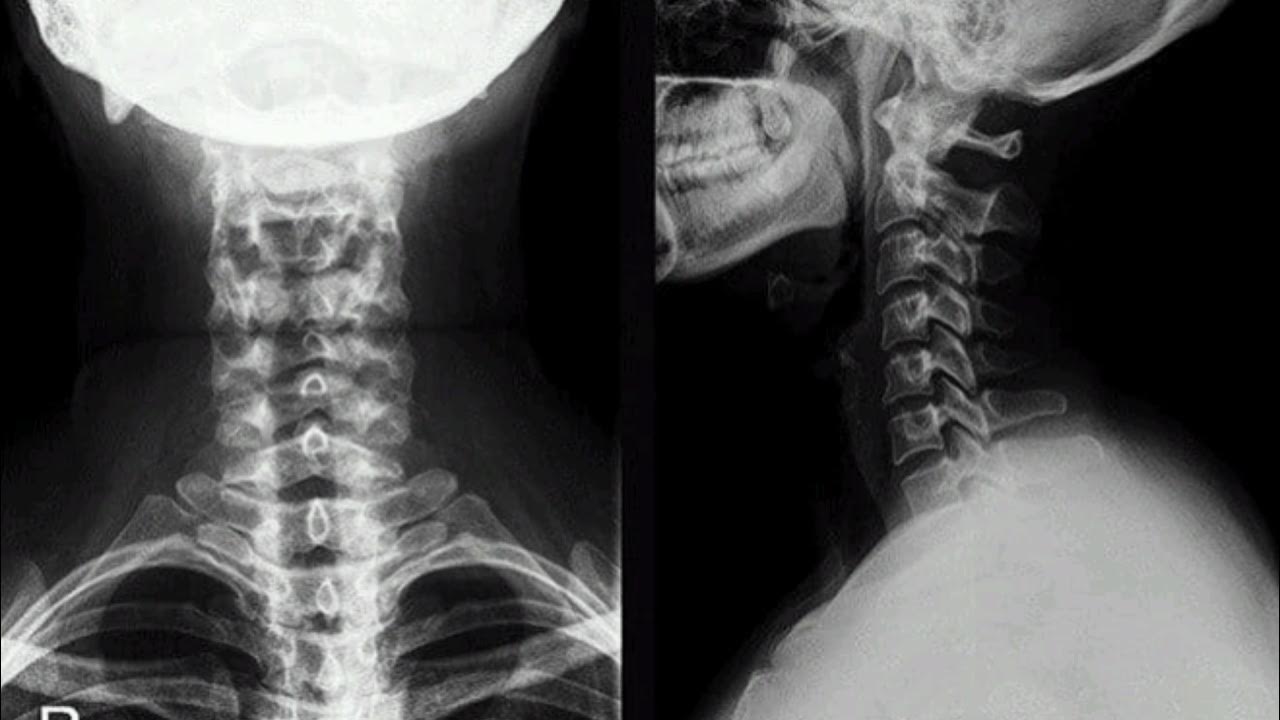

Медицинские снимки: рентген позвоночника сбоку